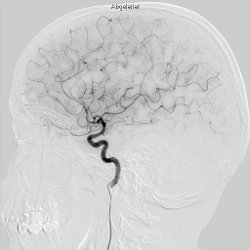

Angiographie

Neuroradiologie